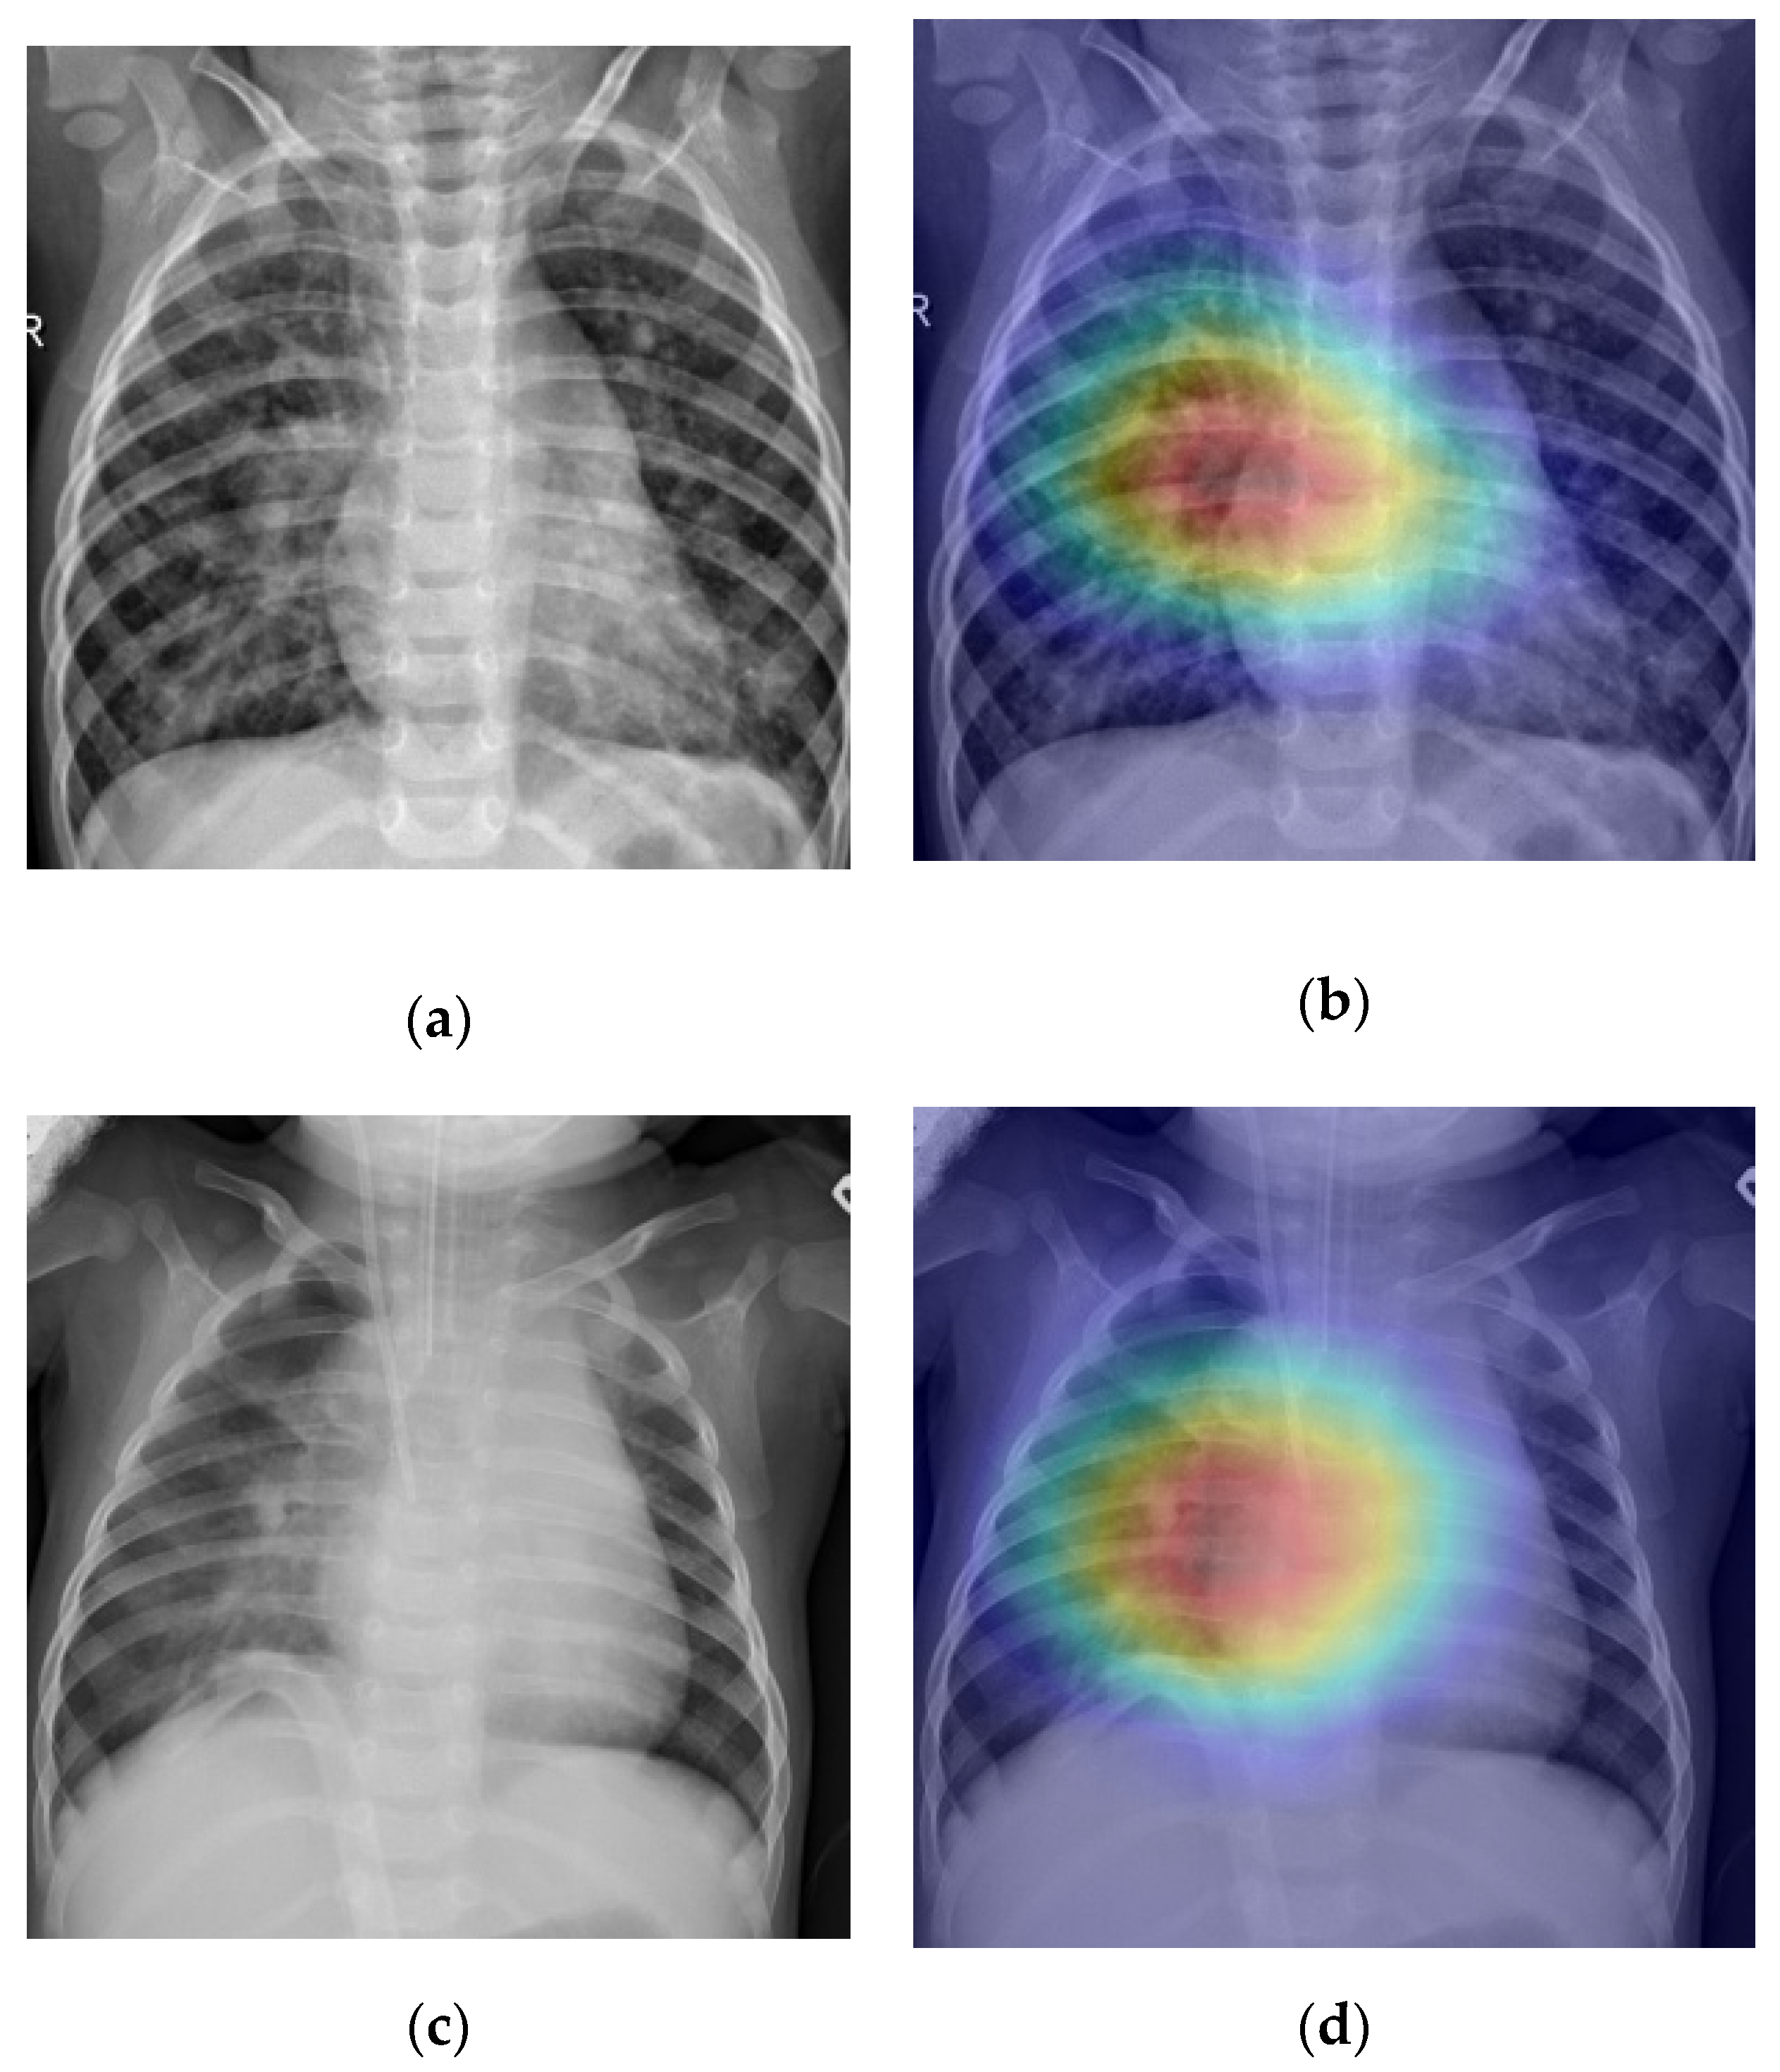

3.5. Screening and Localization

- Grad-CAM generation for test examples.

5.4. Disease Screening